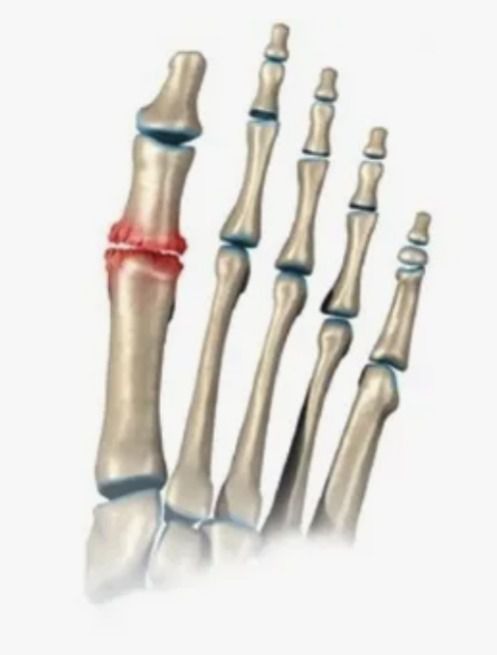

Пфс 1 пальца

Пфс 1 пальца 143 фото